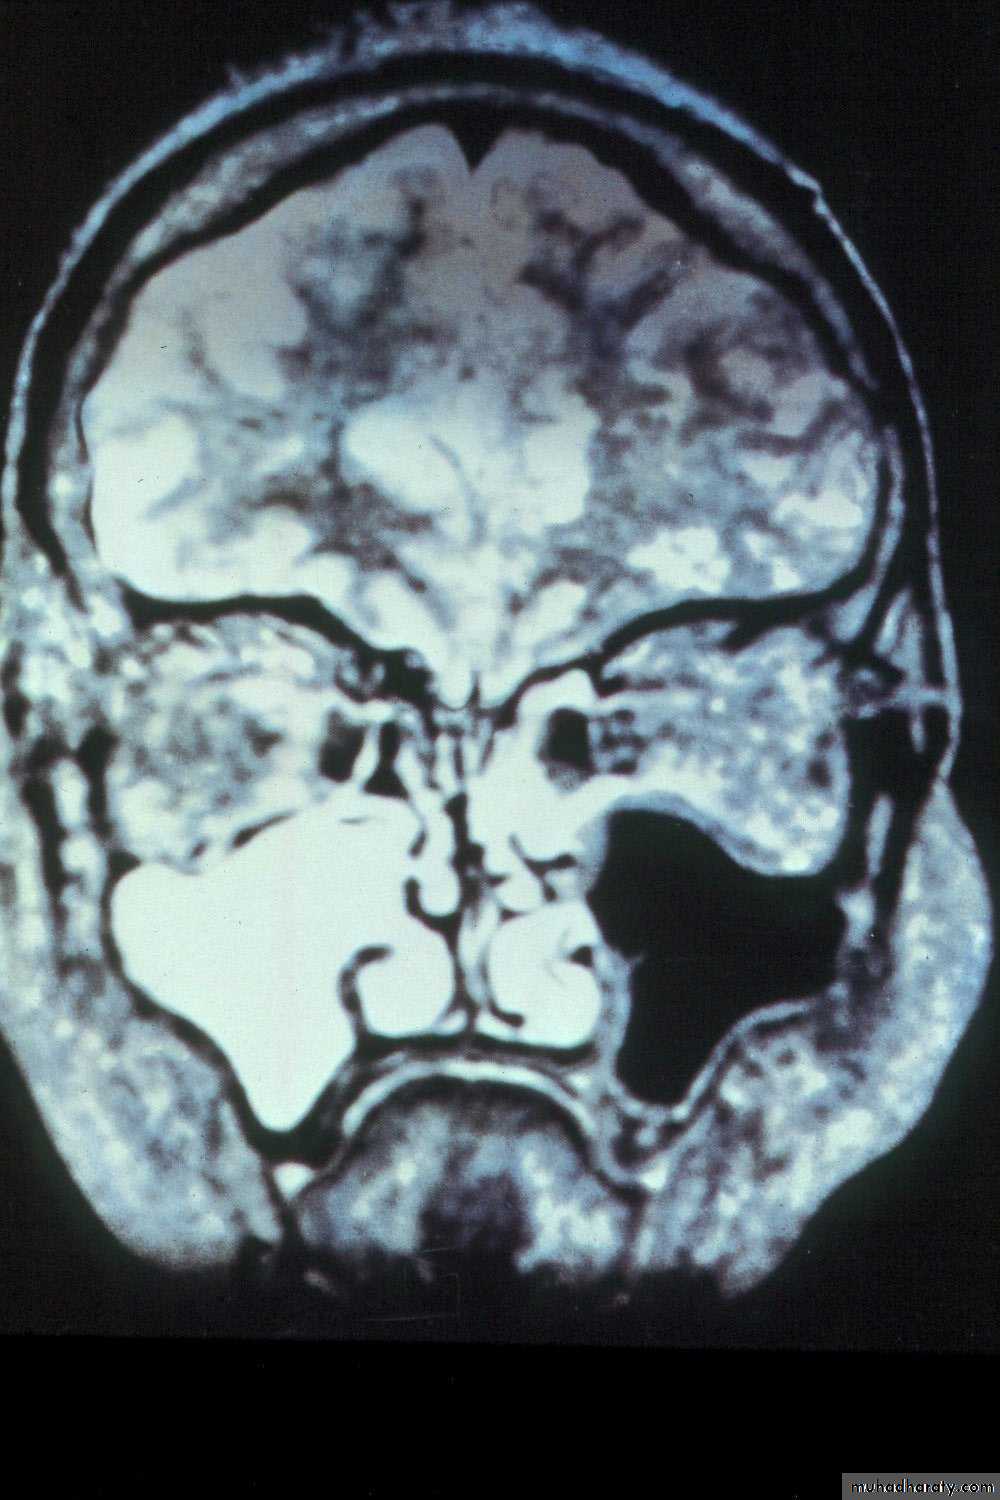

Coronal MRI scan showing maxillary sinusitis